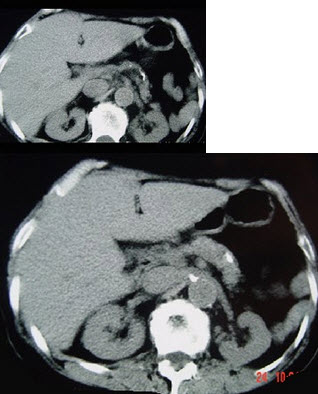

女,54岁,中上腹痛,体重减轻,消化不良,脂肪痢、便量多、泡沫状。影像检查如下图,最佳诊断是( )

A:急性胰腺炎

B:慢性胰腺炎

C:胰腺癌

D:急性出血坏死性胰腺炎

E:胰岛素瘤